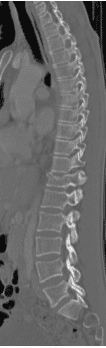

48 yo Female had a sledding injury when she landed on her buttocks following a fall. She felt a “pop” and immediate back pain. She was able to walk briefly, but quickly incapacitated by pain. Her examination suggested an injury to the lower thoracic spine. She was neurologically intact. She had uncontrolled pain. X Rays and CT scan of the patient showed fracture of T12 vertebral body.

The fracture was stabilized by Minimal Invasive spine surgery with percutaneous pedicle screws in T11, 12 and L1 and rod fixation.